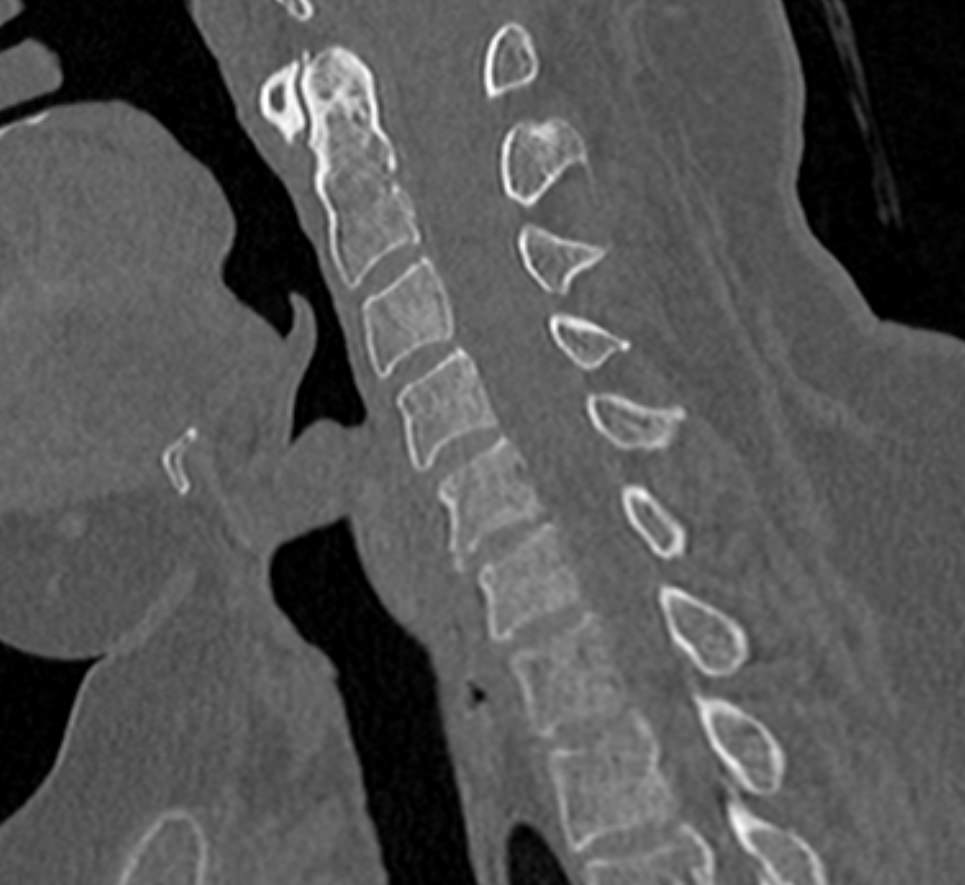

Для диагностики даже незначительных патологических изменений в различных отделах позвоночника, особенно в случае распространенного поражения, применяется один из современных наиболее информативных методов обследования – мультиспиральная компьютерная томография всего позвоночника. Методика основана на использовании проникающей способности рентгеновских лучей через органы и ткани человека и позволяет получить подробное изображение всех структур позвоночного столба. В комплексное обследование входит исследование шейного, грудного, пояснично-крестцового отделов позвоночника и копчика.

- дегенеративно-дистрофические заболевания позвоночника (остеоартроз, спондилез, деформирующий спондилоартроз);

- травматические повреждения позвоночника (компрессионные и оскольчатые переломы);

- стеноз (сужение) позвоночного канала;

- грыжи межпозвонковых дисков (протрузии, экструзии и грыжи Шморля);

- патологические изгибы позвоночника, сколиоз, усиленный или выпрямленный лордоз как нарушение статической функции позвоночника;